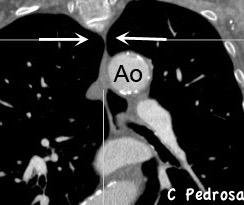

26. AORTA “ESTRECHA” SIGNO DE LA

(“Skinny aorta”)

Aortitis extensa

Enf. de Takayasu.

(Mujeres, 2ª y 3ª décadas)

Coartación aórtica

Pseudocoartación

Vasculitis de grandes vasos

Rotura aórtica

Compresión extrínseca

Radioterapia

Neurofibromatosis

Basado en Kicska G. Narrowed aorta. Stern-Gurney. Expertdd.Chest. Marisys. 2011